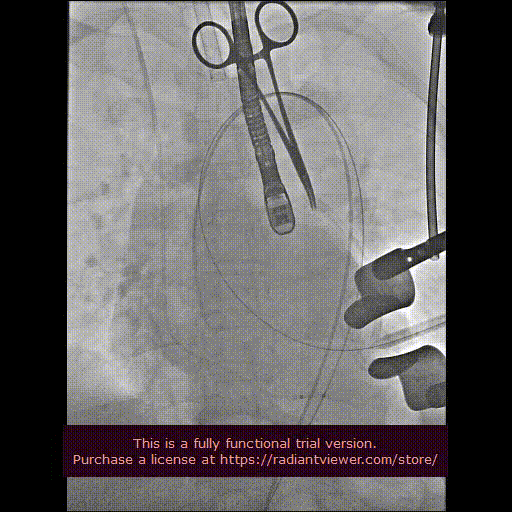

用经胸超声心动图确定心尖位置,并做好标记。常规肝素化,按照心尖标记,行第5、6 肋间左胸前外侧小切口,充分暴露心尖后将心包切开并悬吊,用3-0 Prolene 线加毛毡片完成荷包缝合。经股动脉植入6Fr鞘管,并插入猪尾造影导管至主动脉根部,造影确定主动脉瓣瓣环水平及两侧冠状动脉开口。

经心尖途径置入 J-Valve 瓣膜输送系统,在升主动脉部打开定位件,调整角度,轻轻向后牵拉输送器使定位件进入主动脉窦内。联合主动脉根部造影和食管超声观看定位件是否定位于窦底,形态随着心脏跳动而自然摆动即可。下降瓣膜至主动脉瓣环内,在主动脉瓣口释放瓣膜支架,此过程无需快速起搏。瓣膜成功释放后移除瓣膜输送系统。行主动脉根部造影及经食管超声检查,对瓣膜功能、位置情况进行术后即刻评估。确认位置良好、功能正常后,移除导丝及输送系统,并收紧心尖荷包缝线打结固定。

从心尖置入输送系统

定位件入窦